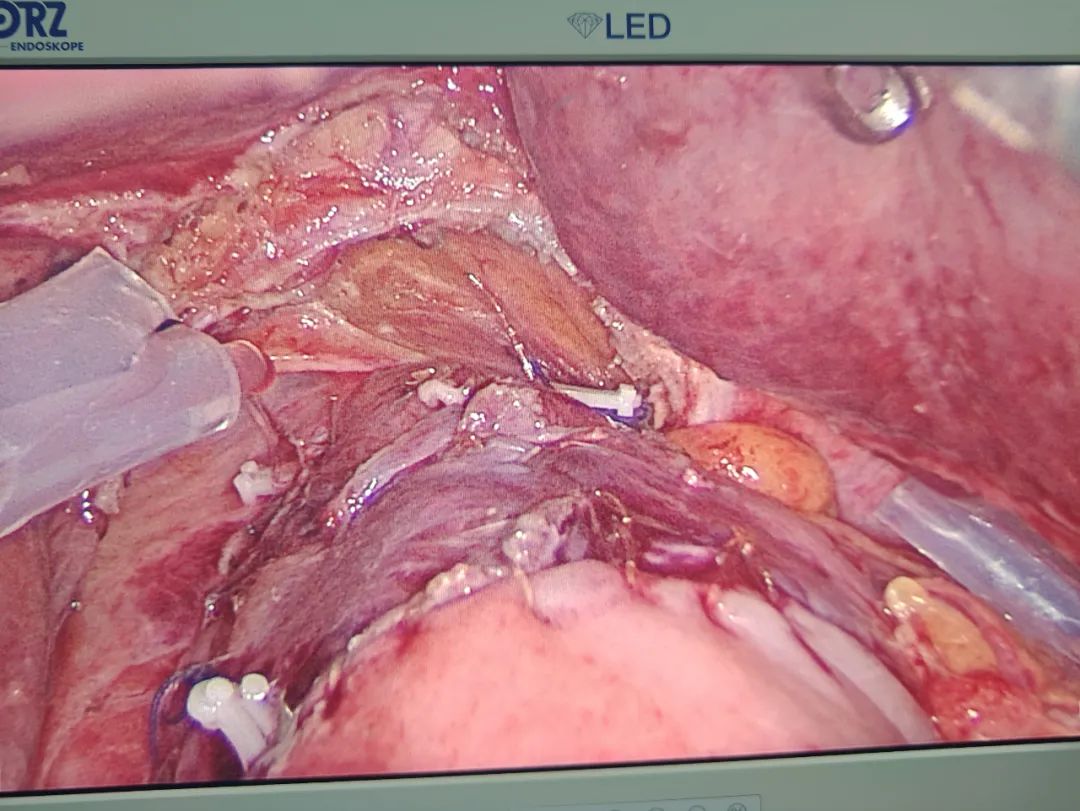

科室團(tuán)隊(duì)針對(duì)吳奶奶的病情開展了疑難危重病例討論,制定嚴(yán)謹(jǐn)、規(guī)范的手術(shù)——腹腔鏡輔助胃癌根治術(shù)(Kamikawa吻合)。黃賢強(qiáng)主任帶領(lǐng)團(tuán)隊(duì)精細(xì)操作,順利完成手術(shù)。

? ??

(食管胃雙肌瓣吻合)